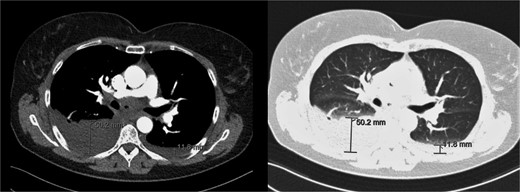

Additional imaging diagnostics with X-ray demonstrated bilateral pleural effusion, more apparent at the right side (Fig. 1). A subsequent computed tomography (CT) scan showed no signs of pulmonary embolism and confirmed the pleural effusion (Fig. 2). In addition, air was seen in the anterior mediastinum (pneumomediastinum). Both air and pleural effusion were attributed to normal healing after the recent VAMLA, and in the absence of clinical alarm symptoms the patient was sent home. In the absence of loculation or contrast captation, the bilateral pleural effusion had no radiological signs of empyema. One of the symptoms of pleural effusion is dyspnea which was also present in the patient. In addition, there was no suspicion of an infectious cause with normal vital values with a temperature of 37.7°C and no significant elevation of WBC or CRP. It was suspected that the effusion was postoperative or reactive to the suspected lung cancer. Regarding the hoarseness, the most likely cause was post-operative swelling of the surgical area. As the hoarseness did not occur immediately post-operative, iatrogenic recurrent nerve injury was not suspected.

Chest X-ray during visit to the emergency department showing bilateral pleural effusion.